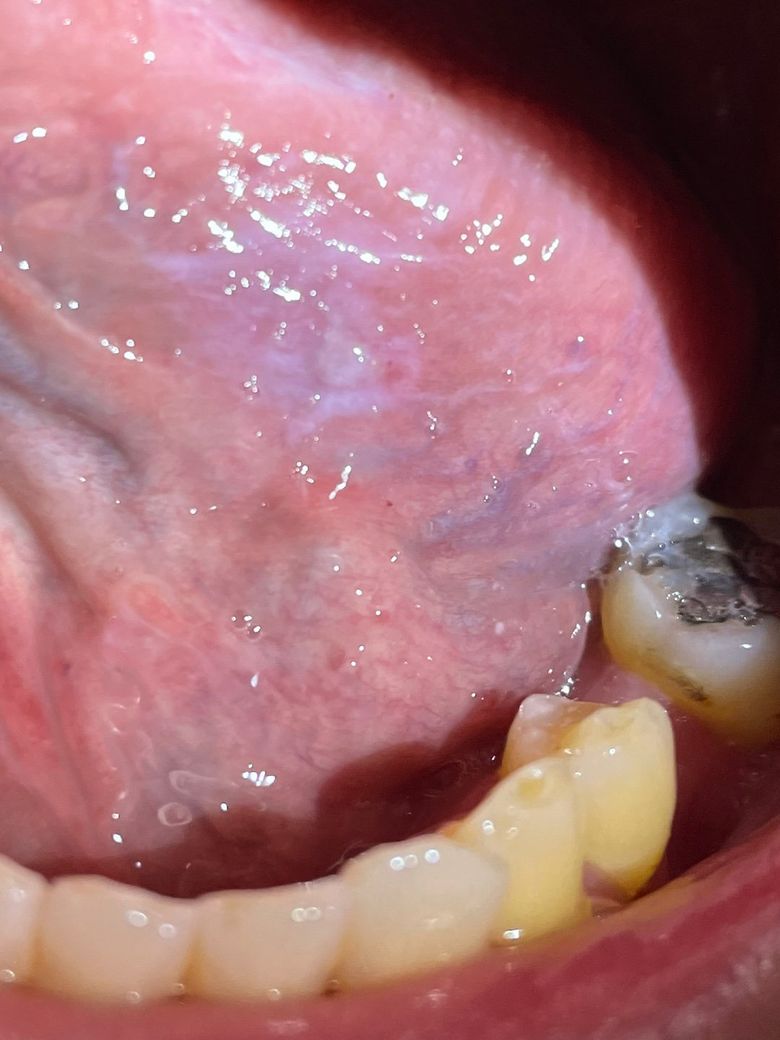

하얀부분은 치유되는 중인가요?

몇일전 자다가 깨물어서 상처가 났는데

그 검은 상처가 없어지고 하얗게 변해있더라구요

그리고 군대군대 검은 작은 상처들이 보이긴 합니다

상처로 인해 과각화가 진행되어 하얗게 변한것으로 판단됩니다.(신체가 외상에 대처하기 위해 방어벽을 두껍게 세운 상태라고 보시면 됩니다.)

혀 밑쪽에 난 상처로 보이며, 이상처가 잘 아물고 있습니다. 혀에는 혈관분포가 많기 때문에 상처가 쉽게 아뭅니다.

하얗게 보이는 것은 그부위에 상처가 아물면서 각화층이 생긴 것입니다.

정상적인 외상 이후 치유 과정 중 하나로 보여집니다. 특별히 해당 부위 주변에 발적이나 부종 등이 없으며 잘 회복되고 있는 것으로 보입니다. 말씀하신 것은 설정맥류로 인하여 나타나는 것일 수 있으며 전혀 문제가 되지 않습니다.